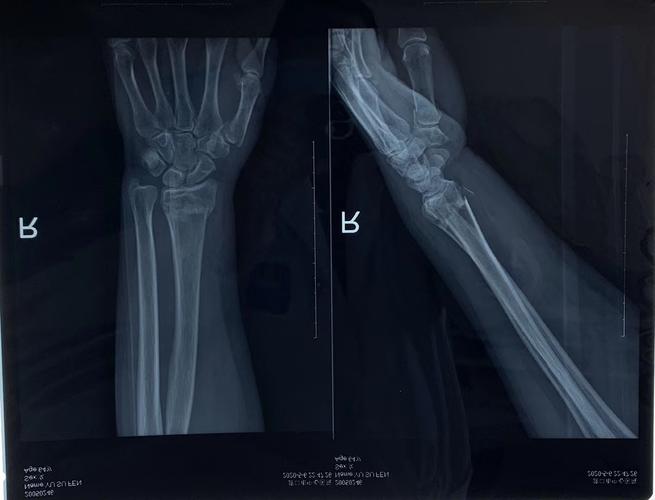

桡骨远端骨折

左手桡骨错位骨折

左桡骨远端骨折

左尺桡骨远端骨折图片

左手桡骨远端骨折图

左侧桡骨远端骨折图片